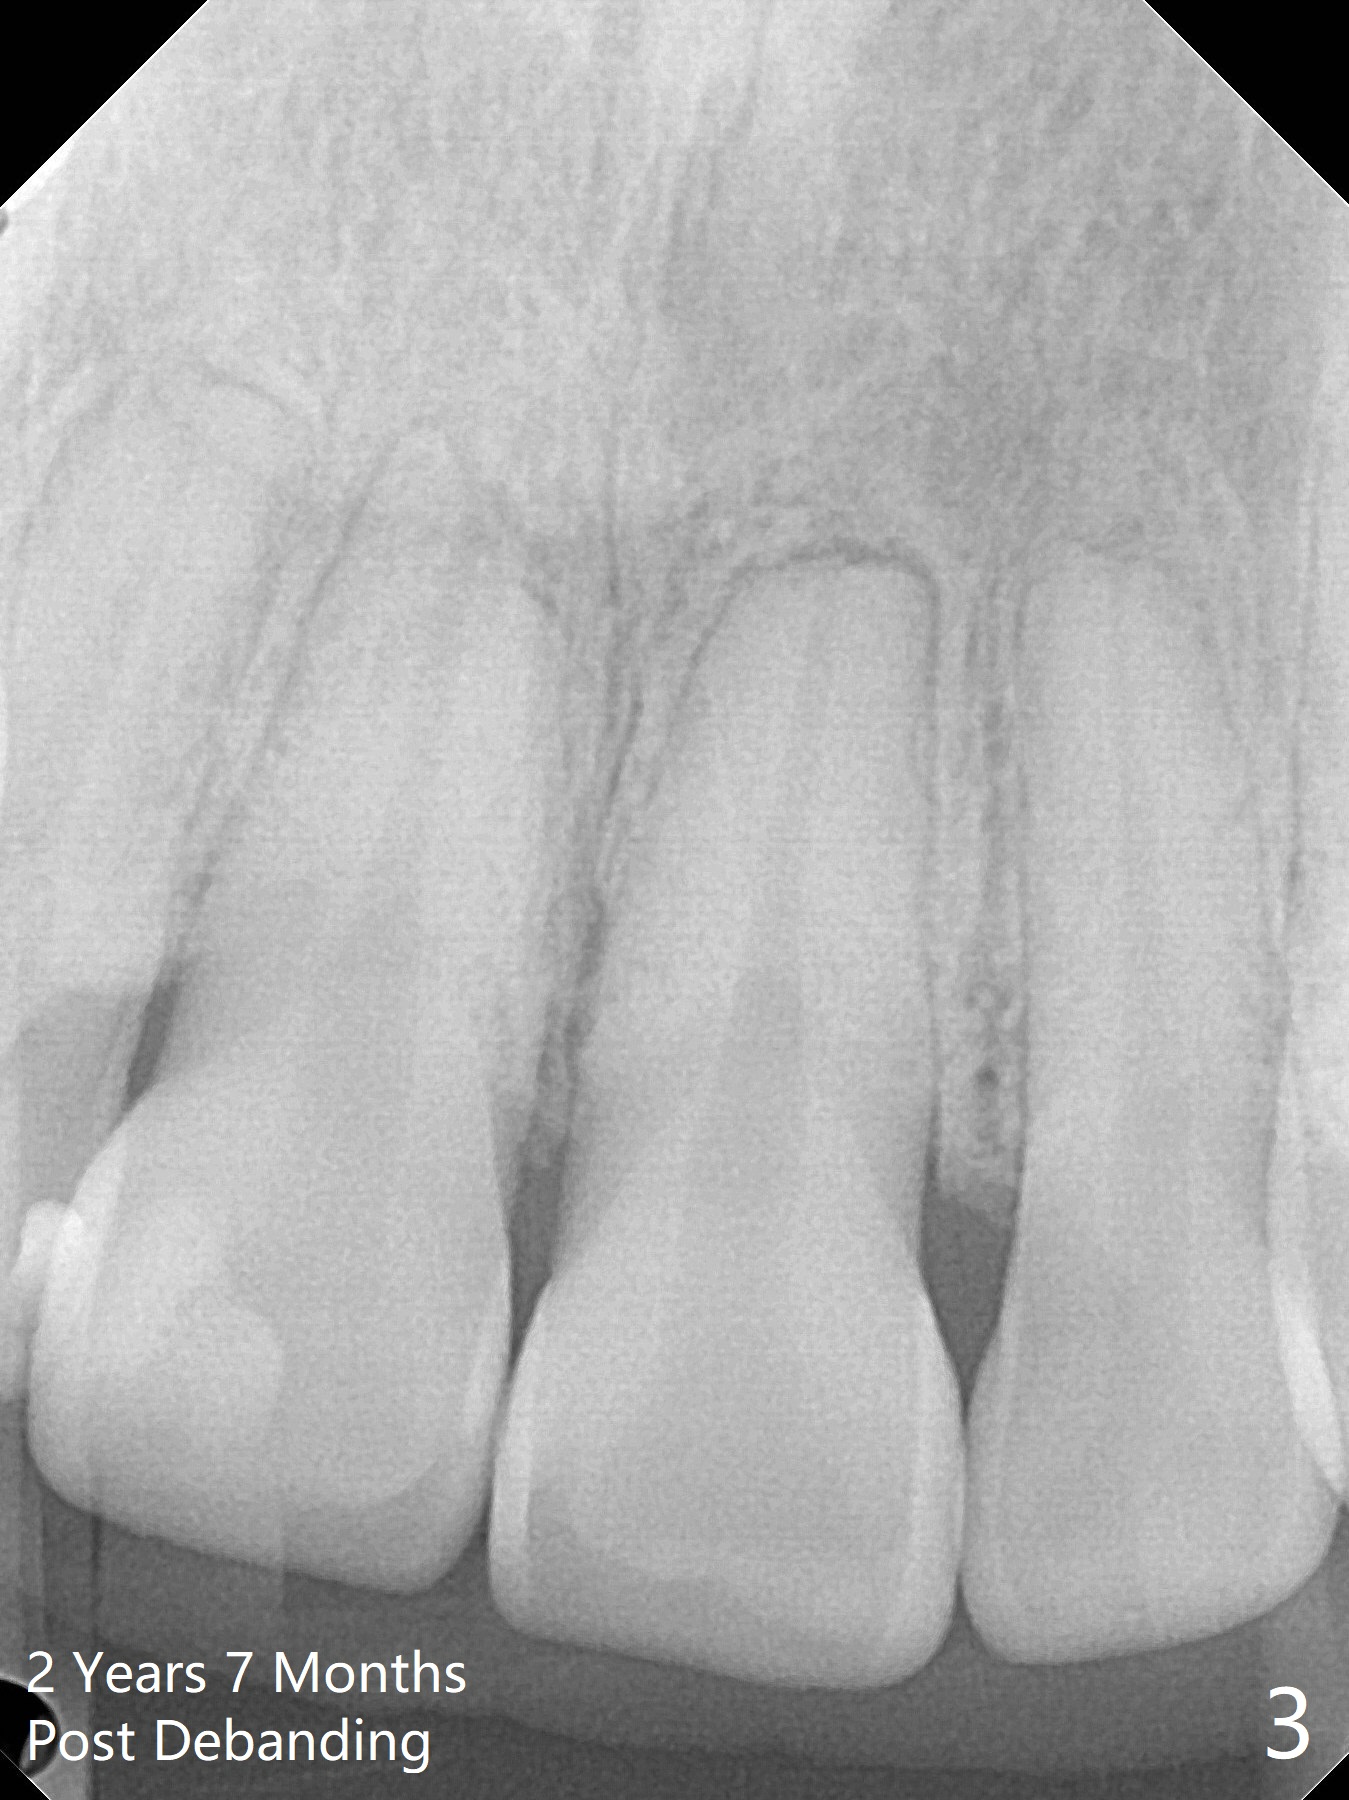

2 Years 7 Months Post Debanding

Return to Ortho Cases 植牙,导板与正畸 Five months post debanding 3 Years Post Debanding